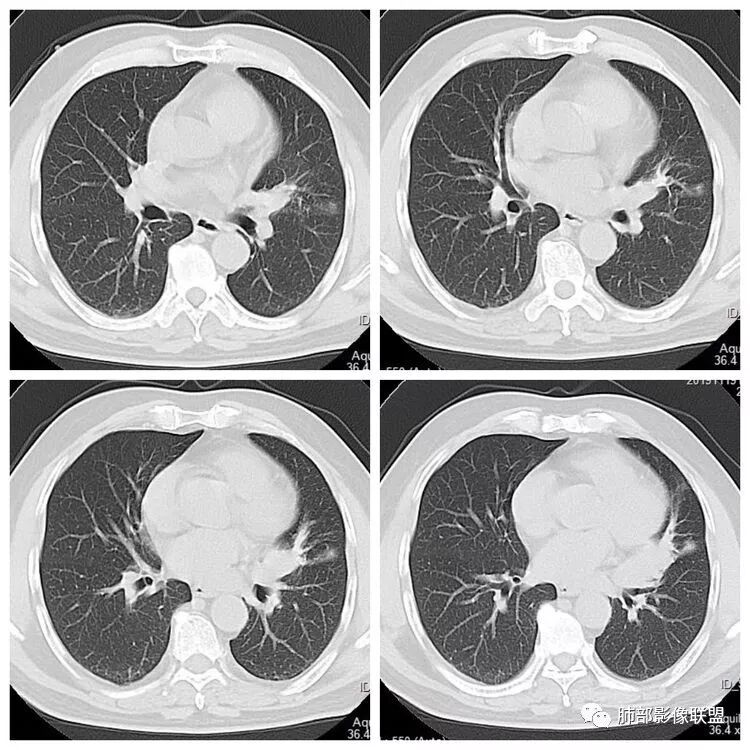

左肺下叶占位,左肺下叶前内支气管阻塞可疑(缺乏薄层),病灶有膨胀性,远端较内侧细,增强病灶强化不明显——乏血供病灶,病灶沿支气管生长,考虑恶性病变,左肺上叶可见小结节病灶,边缘光滑清晰,考虑转移瘤,综上所述考虑恶性病变,左肺下叶小细胞类癌可能,左肺上叶转移。

左肺下叶结节支气管进入截断,远端肺不张,增强后坏死不均匀,肺癌明显,至于病理类型,鳞癌,小细胞,腺癌都有支持和不支持的地方,个人倾向于鳞癌可能,理由,纵隔淋巴结肿大不明显,远端阻塞性不张,支持小细胞的地方,坏死呈沼泽样,但纵隔无明显淋巴结肿大及冰冻表现。腺癌这种表现一般为低分化腺癌,但远端阻塞性不张及纵隔无明显淋巴结肿大不支持。

1.主病灶明显堵塞支气管,我觉得如果结核爬行,应该是外向内爬,这个我觉得是内向外堵塞,而且爬行的结核一般是肉芽肿,不是坏死,增强不会这么低,这个密度和强化比较符合一个坏死。最重要鉴别,结核的爬行是外向内,周围有树丫。这个是内向外,支气管堵塞且坏死明显,外周的堵塞性肺不张,没有树丫,所以主病灶考虑内向外,故结核爬行不太符合。而中央型腺癌不是没有,而是少,加上坏死这么明显,淋巴结转移不明显,故猜测鳞癌或者唾液腺肿瘤可能性比较大,因为后者也是支气管中央起源,强化比较弱的。腺癌和小细胞不太典型,类癌可以表现为支气管粘液栓,但是强化不够。

2.病灶在平扫时似乎软骨在病灶外,提示病灶位于支气管内?这个可以仔细观察一下。

3.至于那个结节。是否一元不太好说。给的不是薄层似乎,强化没有说。目测是一个比较光滑的病变,有微分叶。那套路就是判断与支气管血管关系看看。血管关系很重要,错构瘤是推移,psp是贴边,转移应该会有血供,血管会增粗,这个需要细节。孤立结节疾病谱有错构瘤,psp,肺本身另外一个肺癌,转移,结核球。也可以从这个病灶入手

初学者:这个结节里面点状高密度究竟是血管还是钙化,视频看不清楚,大家可以讨论一下。很有帮助下面这个图可以看到病灶整体有彭隆以及强化不均血管如果给我重建一下就好了,如中央钙化,强化弱,又血管推移,边缘这么光滑的又钙化,一般概率上良性的错构瘤最多,转移保险起见要排一排。

1.定位:左肺块影同时累及下舌段及下叶内基底段且相互延续。病灶跨叶,或存在叶裂发育异常,或者说就是病灶的肺门蔓延。

2.病灶前上部分与舌段支气管相关且形成阻塞。

3.左肺上叶另见孤立结节影,边界清楚光整,中央钙化,未见脂质密度特征。

6.分析:男性患者,左肺门区块状影,支气管阻塞,强化不显著,未见淋巴结肿大,更多见于肺鳞癌。难以解释的是下肺病灶的生长方式。

沿肺门或是叶裂缺损孤立发生且蔓延,转移性腺癌似乎可以解释,但占据较大支气管腔就属罕见了。

7.左肺上叶孤立小结节影中央钙化可见于肠道肿瘤,但更多见于错构瘤,或是结核球。